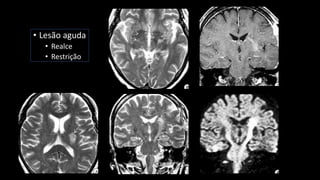

Degeneração Walleriana

• Lesão aguda

• Realce

• Restrição

• Lesão aguda •Realce • Restrição